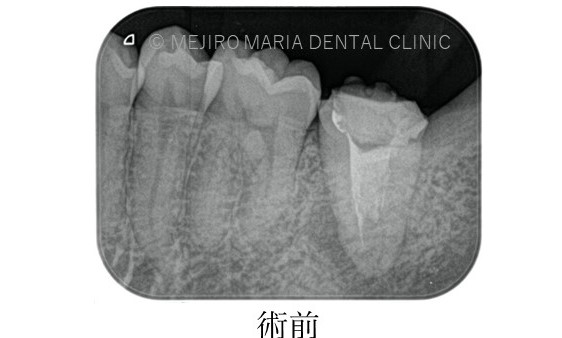

に対する、精密根管治療のアプローチ(再根管治療)_治療前のレントゲン画像1.jpg)

に対する、精密根管治療のアプローチ(再根管治療)_治療前のレントゲン画像2.jpg)

前医にて根管治療を終了したが、痛みと違和感に改善がないため来院された患者様です。前医では樋状根(といじょうこん)の為、これ以上の治療はできないと言われ、抜歯を勧められていました。

根尖性歯周炎は細菌が原因であるため、根管治療にてできる限り細菌を除去することが必要になります。しかしながら、樋状根(Cシェイプ)は根管の大部分が根内部でつながっている形態をしているため(写真2)洗浄が非常に困難です。

また、今回のような樋状根(Cシェイプ)は内側の隆起している部位(写真2赤丸部位)など、歯質が非常に薄い形態をしていることからむやみに削合を行うと穿孔(読み:せんこう パーフォレションともいわれ、歯に穴をあけてしまうことを指す)を起こしてしまう可能性も高くなります。